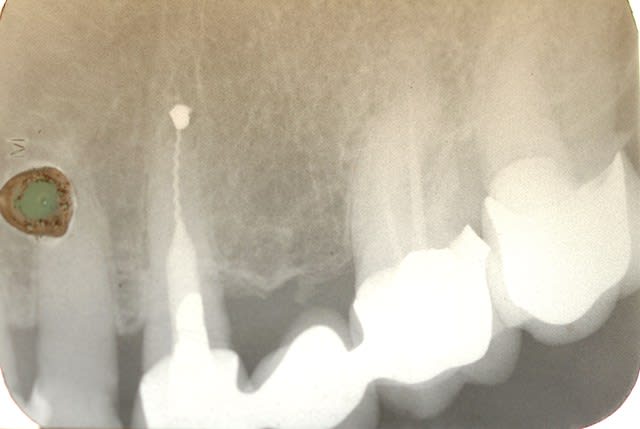

Euh .......les gas y a pas un truc qui vous gêne là ? Vous avez vu les radios ?

Premièrement il faudra que m'expliquer comment le bridge qui au départ est infiltré voir carié sur la 4 se retrouve comme par magie ré-adapté.

Le tenon n'est pas le même

Le traitement endo n'est pas le même

La 7 est couronnée (cantilever) sur une radio , pas sur la radio pré-op

Le niveau osseux n'est pas le meme sur les 2 radios

BREF IL NE S'AGIT PAS DU MEME PATIENT....

Tu dis avoir démonté le bridge et reposé tel quel , ce qui est faux au vu de la radio pré-op en page 5..... le tenon , ete le trt endo sont différents .

Tu as donc inventé une technique pour réadapter des prothèses non adaptées ....... le hyatus a disparu comme par magie , donc 2 possibilités :

- Tu as refait le bridge et tu ne le dis pas

- La radio pré-op est de quelqu'un d'autre

Les autres radios je m'en fous , je dis juste qu'entre les deux radios (15 ans) il y a du y avoir une intervention divine ....

Je te trouve bien hargneux sur ce bridge, parce que si tu regardes bien les radios tu vois bien que c'est le même patient quand-même, et que la 7 a été couronnées par la suite. Les radios ont une incidence un peu différente.

Si 15 ans sépare la radio pré opératoire de la dernière radio, force et de constater que la réimplantation a fonctionné.

Je note néanmoins une cratérisation apparue autour de la partie cervicale de la racine réimplanté, suite à l'intervention, mais stabilisée par la suite.